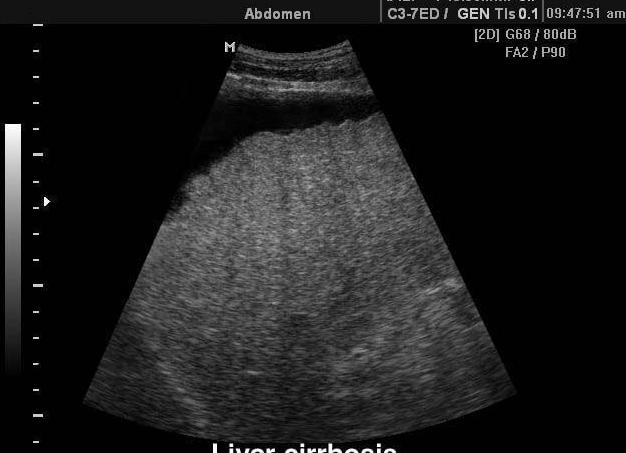

Цирроз печени на узи

Показатели УЗИ при циррозе

Первое, что обращает на себя внимание при исследовании любого внутреннего органа, — размер. При циррозе чаще всего печень увеличивается, но в последней стадии она атрофируется (уменьшается в размерах) и сморщивается. В период разгара заболевания на УЗИ заметно, что левая и хвостатая доли увеличены, а края и контуры органа изменены. При маленьких узлах эти признаки могут отсутствовать. Для остальных форм заболевания характерно наличие бугристого контура и тупого края.

При дифференциальной диагностике гепатита и цирроза эти особенности являются самыми важными. Такие признаки, как наличие бугристого контура и регенерации в виде узлов, будут говорить о более серьезной болезни.

Система кровоснабжения печени также претерпевает изменения. В отличие от нормального мелкого сосудистого рисунка появляются обедненные черты, вены внутри печени имеют непостоянную ширину. Диаметры селезеночной и воротной вен, а также печеночной артерии, увеличиваются. Наблюдается соединение сосудов брюшной полости, не свойственное здоровому человеку. В селезеночной вене ток крови уменьшается либо останавливается, возможно обратное движение.

При образовании рубцовой ткани УЗИ показывает различную плотность паренхимы. Неоднородная структура будет причиной разного прохождения ультразвуковых волн через ткань. В таком случае достаточно просто не заметить или ошибочно определить наличие опухоли.

В 90% случаев на фоне цирроза происходит увеличение селезенки более 50 см². При развитии болезни появляются признаки распространения патологического процесса в брюшной полости в виде отеков желудка и кишечника. В дальнейшем виден асцит, что говорит о накоплении жидкости в животе и последней (терминальной) стадии.

1. УЗИ при циррозе печени нередко позволяет поставить окончательный диагноз, особенно в период декомпенсации. При легкой степени цирроза УЗИ покажет увеличение печени, но структура ее будет еще однородной. При субкомпенсации и декомпенсации картина более характерная. Если цирроз мелкоузловой, то фиксируется увеличение эхогенности печени равномерного характера. При крупноузловом циррозе печени УЗИ выявит отдельные узлы, неоднородную структуру органа, нередко бугристость поверхности. В далеко зашедших случаях определяется неравномерность долей печени: правая уменьшается. На последних этапах печень бывает даже меньше нормы. Кроме того, УЗИ при циррозе печениуказывает на увеличение селезенки.

При циррозе наблюдается следующая картина на УЗИ:

• увеличение размеров органа за счет преобладания соединительной ткани;

• неровные контуры краев печени (бугристость поверхности);

• неоднородность паренхимы органа, имеются как гипоэхогенные, так и гиперэхогенные очаги, распределенные по всему органу;

• плохая визуализация портальной вены, сосудистый рисунок изменен;

• при синдроме портальной гипертензии наблюдается расширение воротной и селезеночной вены;

• возможно увеличение селезенки.